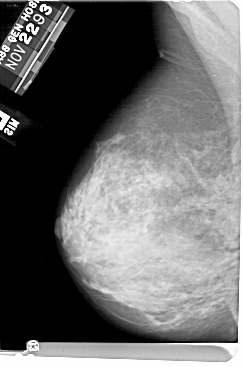

A_1504_1.RIGHT_MLO

RIGHT_MLO LINES 5491 PIXELS_PER_LINE 3421 BITS_PER_PIXEL 12 RESOLUTION 43.5 OVERLAY